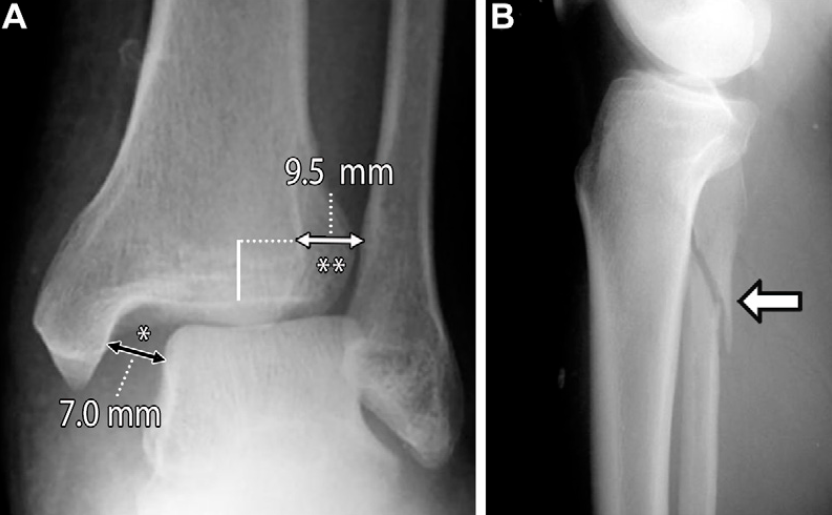

X线片评估胫腓联合分离可通过三项核心测量指标:胫腓重叠距离、胫腓间隙宽度和内侧间隙宽度:

胫腓重叠距离指腓骨远端内侧缘与胫骨远端前结节之间的水平距离,测量点位于胫骨关节面上方10mm处;正位片上该值大于6mm、踝穴位上大于1mm为正常范围 。胫腓重叠距离缺如可能是正常的解剖变异,但踝关节损伤后若出现单侧缺如,应考虑为胫腓联合分离的征象。

胫腓间隙宽度指胫骨后结节外侧缘与腓骨沟最深点内侧缘之间的水平距离,在正位和踝穴位上于胫骨关节面上方10mm处测量,该值≤6mm 为正常;患侧与健侧的胫腓间隙宽度差值≥2mm,可能提示胫腓联合损伤。

内侧间隙宽度指踝关节踝穴位X线片上内踝与距骨之间的距离,该值不应超过4mm,且通常小于或等于距骨穹窿与胫骨平台之间的上间隙宽度。内侧间隙宽度增宽应警惕三角韧带复合体损伤。